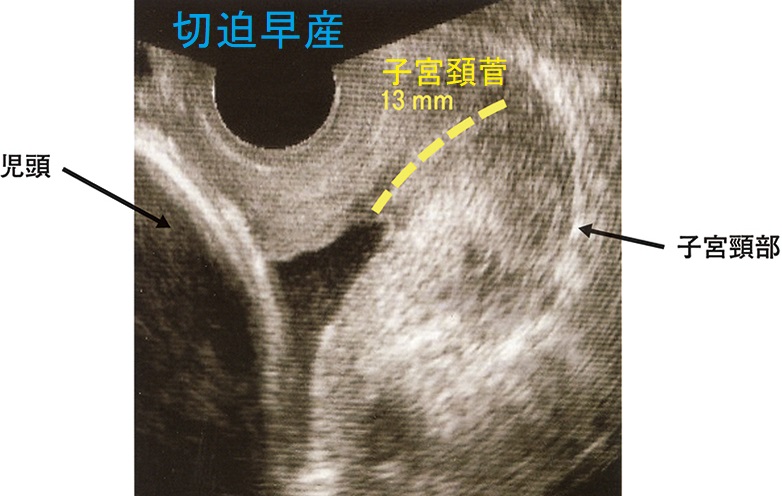

切迫早産 経腟超音波(エコー)検査

切迫早産経腟超音波(エコー)検査

張り止め(子宮収縮抑制薬)のリトドリン(ウテメリン®)、イソクスプリン(ズファジラン®)はβ2刺激剤で、交感神経刺激により子宮の運動(子宮収縮、陣痛)を緩めるため、迫流産切迫早産の予防に使用されます。

そもそも、計画的な妊娠が行われず、切迫流産切迫早産に張り止め(子宮収縮抑制薬)を使用する時期(妊娠16週以降)まで甲状腺機能亢進症/バセドウ病が安定化していない事自体が問題です。本来、甲状腺機能亢進症/バセドウ病妊娠前のブライダルチェックで見つけ、安定させてから妊娠すべきです。

まして、甲状腺機能亢進症/バセドウ病が見つかっていない(未治療の)状態で張り止め(子宮収縮抑制薬)を使用すると、一気に悪化して、命の危険:甲状腺クリーゼ  をおこす危険があります(最悪の事態、妊娠中バセドウ病/甲状腺機能亢進症が発覚し、甲状腺クリーゼ、死戦期帝王切開)。